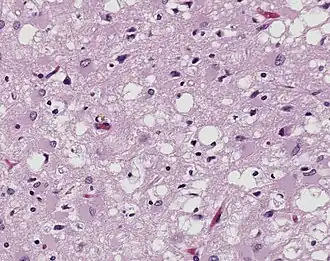

Magnified 100× and stained. This photomicrograph of the brain tissue shows the presence of the prominent spongiotic changes in the cortex, with the loss of neurons in a case of a variant of Creutzfeldt-Jakob disease (vCJD).

Prions are misfolded proteins that transmit their abnormal folding pattern to other copies of the protein without using nucleic acids. Besides obtaining prions from others, these misfolded proteins arise from genetic differences, either due to family history or sporadic mutations.[21] Plants uptake prions from contaminated soil and transport them into their stem and leaves, potentially transmitting the prions to herbivorous animals.[22] Additionally, wood, rocks, plastic, glass, cement, stainless steel, and aluminum have been shown binding, retaining, and releasing prions, showcasing that the proteins resist environmental degradation.[23]

Prions are best known for causing transmissible spongiform encephalopathy (TSE) diseases like Creutzfeldt–Jakob disease (CJD), variant Creutzfeldt–Jakob disease (vCJD), Gerstmann–Sträussler–Scheinker syndrome (GSS), fatal familial insomnia (FFI), and kuru in humans.[24]